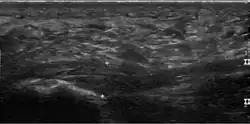

Die Diagnose kann allein aufgrund klinischer Symptome wie dem typischen Fersenschmerz am Morgen und der Druckempfindlichkeit der Fußsohle sowie dem weiter oben beschriebenen Windlass-Test erstellt werden.[5] Da die Dorsalextension des Fußes häufig eingeschränkt ist, gibt es eine Reihe von Methoden, diese zu quantifizieren.[9] Bildgebende Diagnostik mit beispielsweise Sonografie (Ultraschall) wird erst notwendig, wenn die Plantarfasziitis auf konservative Behandlung nicht anspricht und invasive Methoden wie lokale Injektionen erwogen werden.[5] Aus differenzialdiagnostischen Gründen kommen noch andere bildgebende Verfahren zum Einsatz wie die Röntgendiagnostik oder in selteneren Fällen auch die Magnetresonanztomographie (MRT) oder die Skelettszintigrafie.

Im Falle einer Plantarfasziitis zeigt die Ultraschalluntersuchung (Sonografie) eine Verdickung der Aponeurosis plantaris. Die Aponeurosis ist am Ansatz am Fersenbein entweder mindestens 4,0 mm dick oder 0,6 mm dicker als am anderen Fuß.[2] Auch diffuse hypoechogene (im Ultraschall dunkel dargestellte) Flächen werden gesehen, die als Wassereinlagerungen (Ödeme) aufgrund von kleinsten Rissen interpretiert werden.[10] Bei etwa 40 Prozent aller Patienten wird eine erhöhte Durchblutung (Hyperämie) festgestellt, was auf einen akuten Verlauf hinweist. Bei einem chronischen Verlauf wird Hyperämie nicht festgestellt.[10] Die Dicke der Aponeurosis plantaris verringert sich bei erfolgreicher Behandlung, weswegen sie als objektives Maß verwendet werden kann.[2]